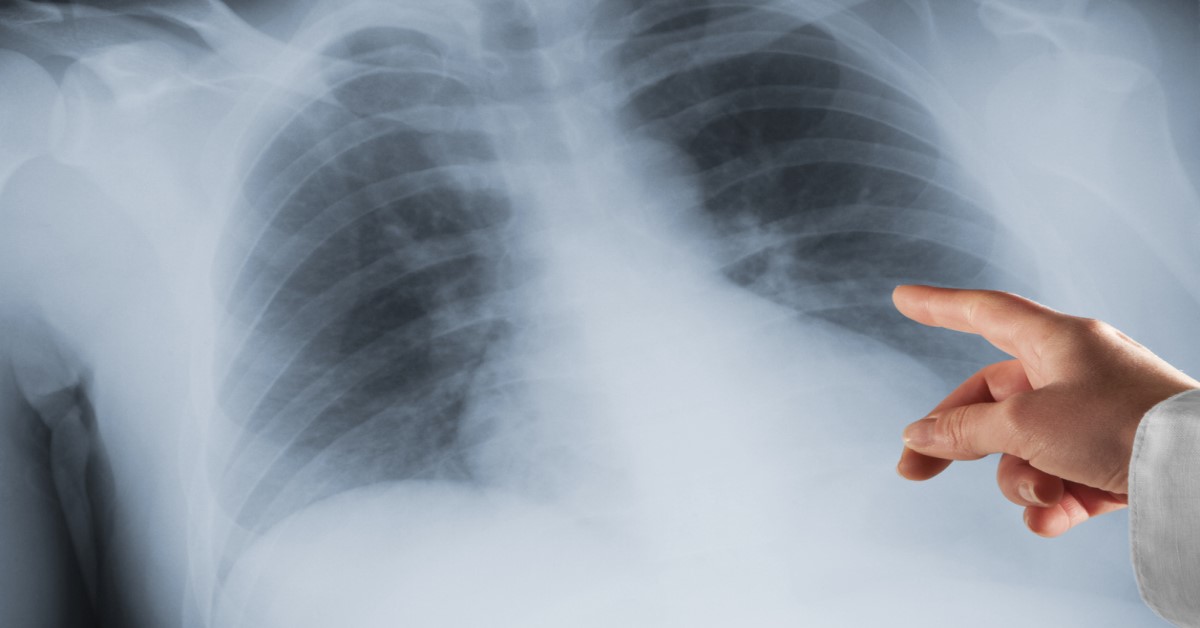

Akciğer kanseri, en korkulan hastalıkların başında geliyor. Akciğer kanserinin diğer kanser türlerine kıyasla ölüm oranının daha yüksek olması endişeye neden oluyor. Uzmanlar, akciğer kanserinin erken evrede tespit edilebilmesi için gereken en önemli kuralın bazı sinyalleri önemsemek olduğunu belirtiyor. Akciğer kanseri, vücutta oluşmaya başladığı andan itibaren bazı sinyallerle ortaya çıkıyor. Zaman zaman soğuk algınlığı sanılan bu belirtiler, ihmal edildiğinde hayati tehlike yaratıyor.

En agrasif kanser türlerinden biri olan akciğer kanseri, direkt akciğerde oluştuysa birincil kanser adını alıyor. Kanser, başka organlarda oluştuysa ve akciğere sıçradıysa ikincil kanser deniyor.

Sağlık alanında yaşanan son gelişmeler sayesinde, akciğer kanseri erken evrede tespit edilebiliyor ve hastanın uzun yaşam şansı artıyor.